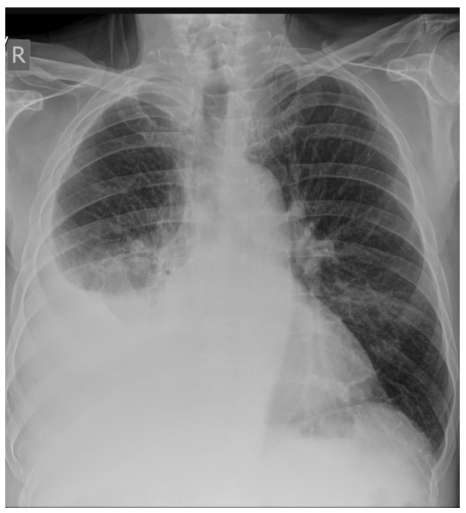

Paciente de 42 anos de idade, do sexo masculino, natural de Minas Gerais, foi trazido pelo irmão à Unidade de Pronto Atendimento devido a tosse secretiva, com início há 12 dias, associada a febre de 38 ºC, além de hiporexia e dor torácica. O paciente relata que já havia procurado a Unidade Básica de Saúde, ocasião em que lhe foi receitado o uso de macrolídeo por 5 dias, não havendo, contudo, melhora significativa dos sintomas.

Os exames laboratoriais do paciente realizados anteriormente apresentaram os seguintes resultados: hemoglobina 13 g/%; leucócitos totais 14.500/mm3; bastões de 5%; neutrófilos 75%; plaquetas 200.000/mm3; ureia 60 mg/dL.

A radiografia de tórax mostrou a seguinte imagem:

Além disso, foi realizada a toracentese para avaliação do líquido pleural, que mostrou: líquido pleural purulento; pH 6,8, DHL 2.000 U/L; proteínas 4,9 mg/dL; glicose 38 mg/dL; predomínio de neutrófilos.

Por fim, o exame físico revelou as seguintes informações:

I O paciente apresenta mau estado geral, confusão, frequência cardíaca de 114 bpm, frequência respiratória de 32 irpm, pressão arterial 90/55 mmHg e saturação periférica de 90% em ar ambiente.

II Aparelho respiratório: sons respiratórios abolidos em base direita; presença de algumas crepitações em região infraclavicular direita; macicez à percussão em base direita, com redução do frêmito toracovocal na mesma região.

III Aparelho cardiovascular: ritmo cardíaco regular em dois tempos, sem sopros; extremidades sem edema de membros inferiores, sem sinais de trombose; e tempo de enchimento capilar de 3 segundos.